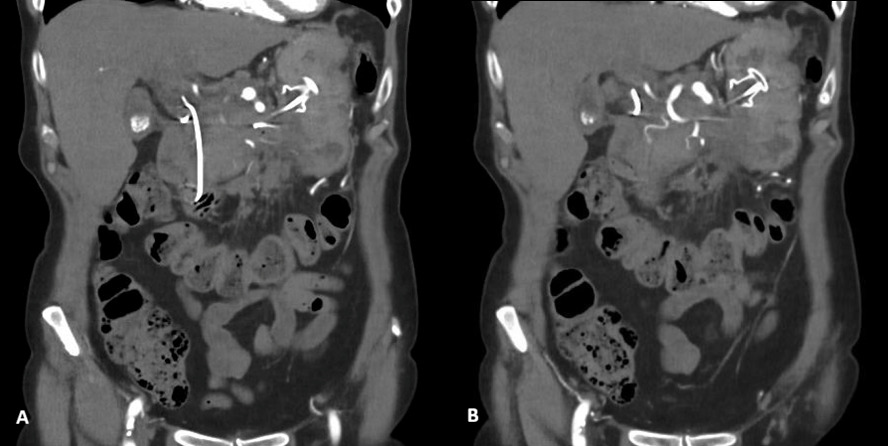

Despite biochemical improvement, the patient’s clinical course was complicated by persistent systemic inflammation and escalating abdominal pain. A contrast-enhanced computed tomography (CT) scan demonstrated features consistent with severe acute necrotizing pancreatitis, including extensive pancreatic oedema, areas of hypo-enhancement, marked peripancreatic fat stranding, and multiple peripancreatic fluid collections. The largest collection measured approximately 10 × 15 × 5 cm (Figure 1).

Ten days following initial presentation, the patient was referred for endoscopic drainage of the peripancreatic fluid collections. Endoscopic ultrasound-guided drainage was performed with insertion of a lumen-apposing metal stent (AXIOS) and an additional plastic stent into the largest collection. A repeat contrast-enhanced CT scan was recommended two weeks following stent placement to assess treatment response (figure 2).